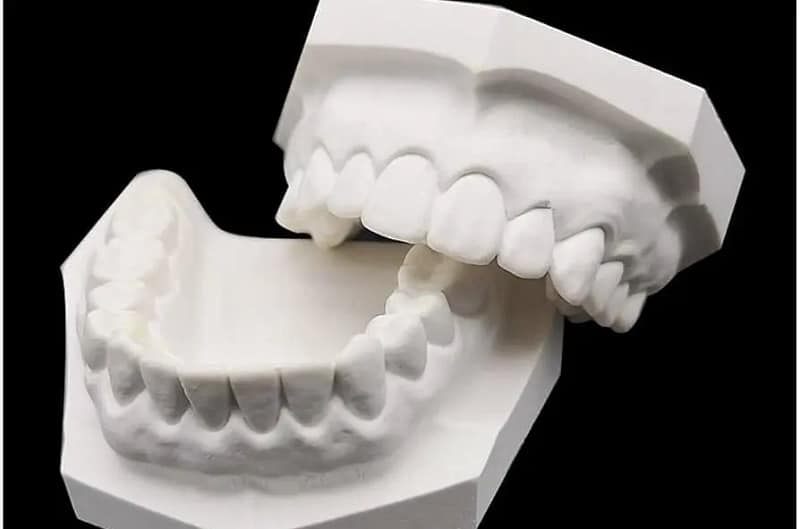

Somos una empresa con más de 5 años ofreciendo servicios de radiología oral y maxilofacial, fotografía intra y extra oral, toma de modelos (estudio y trabajo), análisis cefalométrico por parte de Radiólogos.